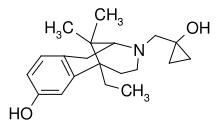

Diphenylpropylamine derivatives

- Propoxyphene

- Dextropropoxyphene

- Dextromoramide

- Bezitramide

- Piritramide

- Methadone

- Dipipanone

- Levomethadyl acetate (LAAM)

- Difenoxin

- Diphenoxylate

- Loperamide (does cross the blood–brain barrier but is quickly pumped into the non-central nervous system by P-Glycoprotein. Mild opiate withdrawal in animal models exhibits this action after sustained and prolonged use including rhesus monkeys, mice, and rats.)